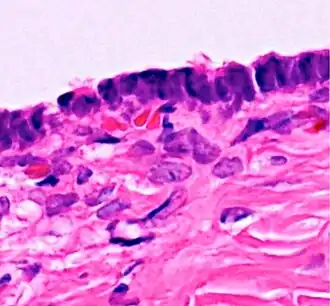

Histopathology of serous cystadenoma of the ovary, which is benign. It shows admixed scattered ciliated cells. This case closely resembles normal surface endometrial epithelium of the uterus.

Histopathology of serous cystadenoma of the ovary, which is benign. It shows admixed scattered ciliated cells. This case closely resembles normal surface endometrial epithelium of the uterus. -